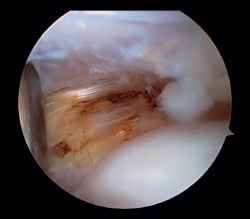

Posteriormente, se realiza la capsulotomía parcial lateral con sinoviotomo o vaporizador, hasta conseguir apreciar el ECRB (Figura 7). Una vez que se consigue su visualización, mediante el sinoviotomo y el vaporizador, se procede a la tenotomía de la inserción del ECRB en el epicóndilo, así como del tejido degenerativo tendinoso asociado (Figura 8). La liberación del tendón del ECRB debe limitarse a una zona anterior al eje central de la cabeza radial con el codo a 90°, para preservar la integridad del ligamento colateral lateral.

Figura 7. Tendón extensor carpi radialis brevis tras capsulotomía lateral (paciente en decúbito lateral, codo derecho, visión desde el portal medial).

Figura 8. Tenotomía del extensor carpi radialis brevis con vaporizador (paciente en decúbito lateral, codo derecho, visión desde el portal medial).